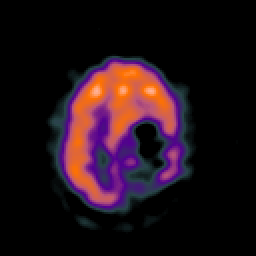

SPECT TC Study #8 -- Slice #39

[Home][Help][Clinical][Tour 1][Tour 2][Tour 3] Slice 39